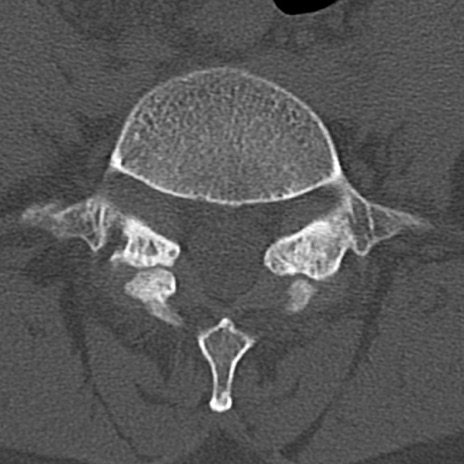

腰椎CT

横断像と矢状断像